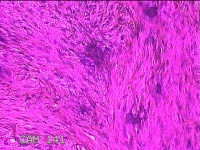

右侧拇指皮下结节

性别

男

年龄

33岁

临床诊断

皮下结节

一般病史

发现右侧拇指皮下结节1年余。

标本名称

大体所见

灰白暗红色带皮肤样结节1x0.5x0.3cm一个,表面糜烂,切开结节呈实性,切面灰白粉红色,质中。